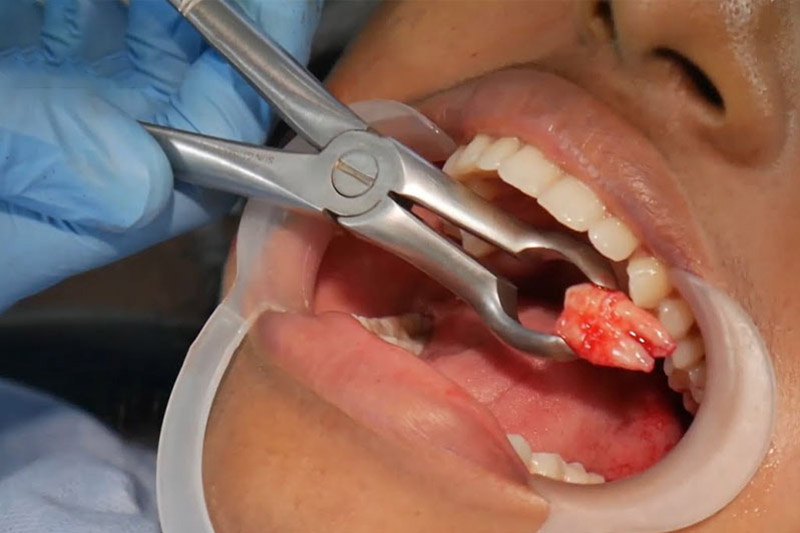

.png)

Hình ảnh răng khôn được lấy ra khỏi hàm